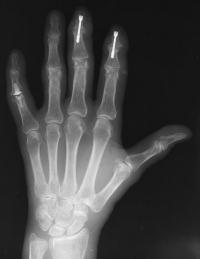

Clinical Example: Distal Interphalangeal Joint Arthroplasty with reversed Ascension carbon implant arthroplasty

These two cases illustrate the use of the Ascension PIP joint implant arthroplasty in the DIP joint position. The stem of the distal component is too wide to fit into the typical distal phalanx, but the proximal component stem will, and in selected cases, the implant will fit in this position if it is placed in a reversed proximal-distal position. These cases illustrate this technique - not as an endorsement, but as a demonstration of  technical feasibility. At one year, each  reconstructed joint was painless and had about 30 degrees range of motion.

Distal interphalangeal erosive osteoarthritis severe enough that the diagnosis of giant cell or other tumor was suspected. Fortunately, no tumor was encountered at surgery.

Final implant radiographs.